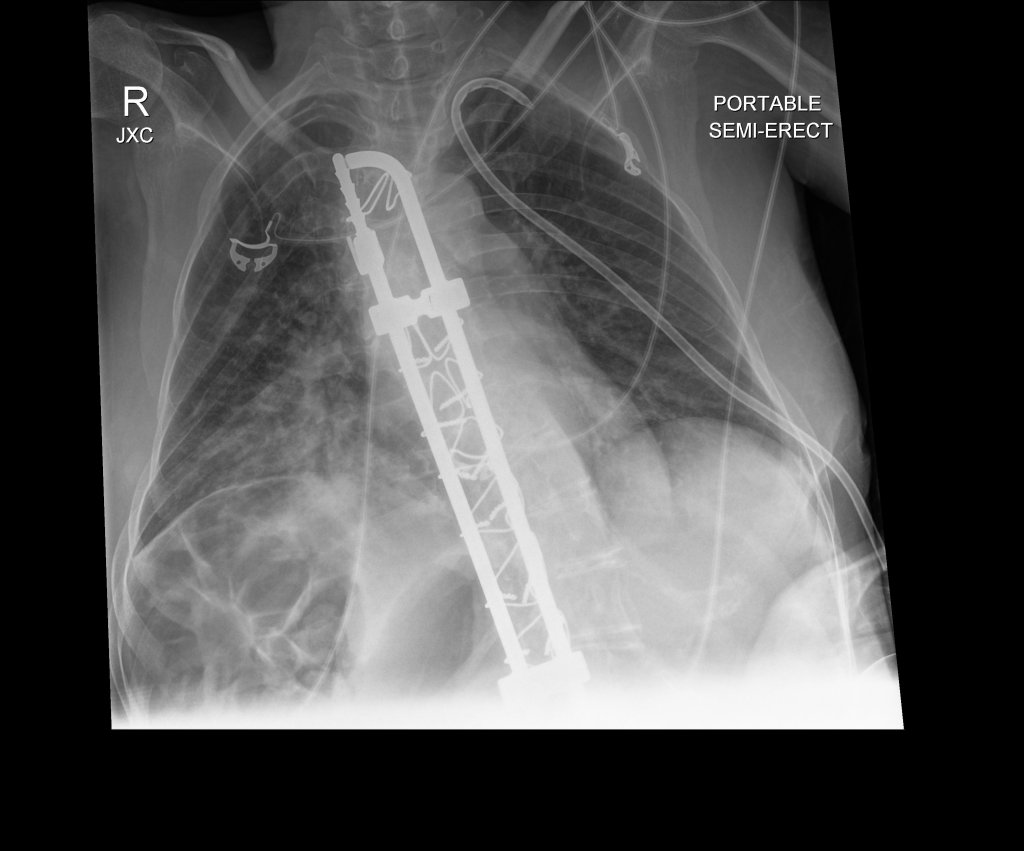

An x-ray revealed I had a pneumothorax, a collapsed lung! Holy shit! I was immediately prepped for a chest tube, the first of a numerous painful procedures I went through. I moved to the intensive care unit (ICU) that night.

Black and white photo of an x-ray of my chest showing some tubes and a metal rod in my spine. Text says, “PORTABLE SEMI-ERECT” and the letters RJXC”